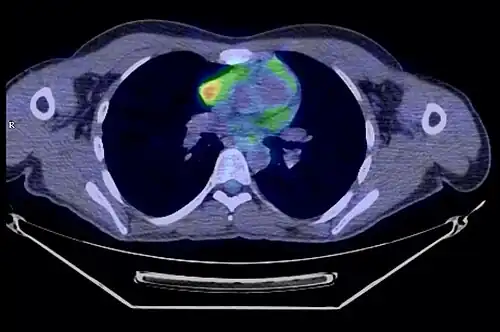

- Thymome de type B1 en TEP scanner

Coupe transversale. Les trois clichés sont extraits du même examen.

Coupe frontale ; la tumeur est à l'intersection des lignes rouges.

Coupe sagittale ; la tumeur est à l'intersection des lignes rouges.